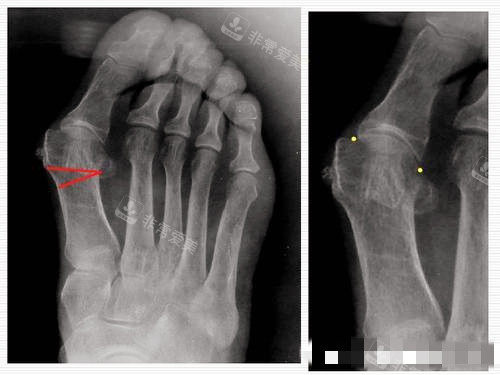

大脚骨X光片图片

大脚骨图片